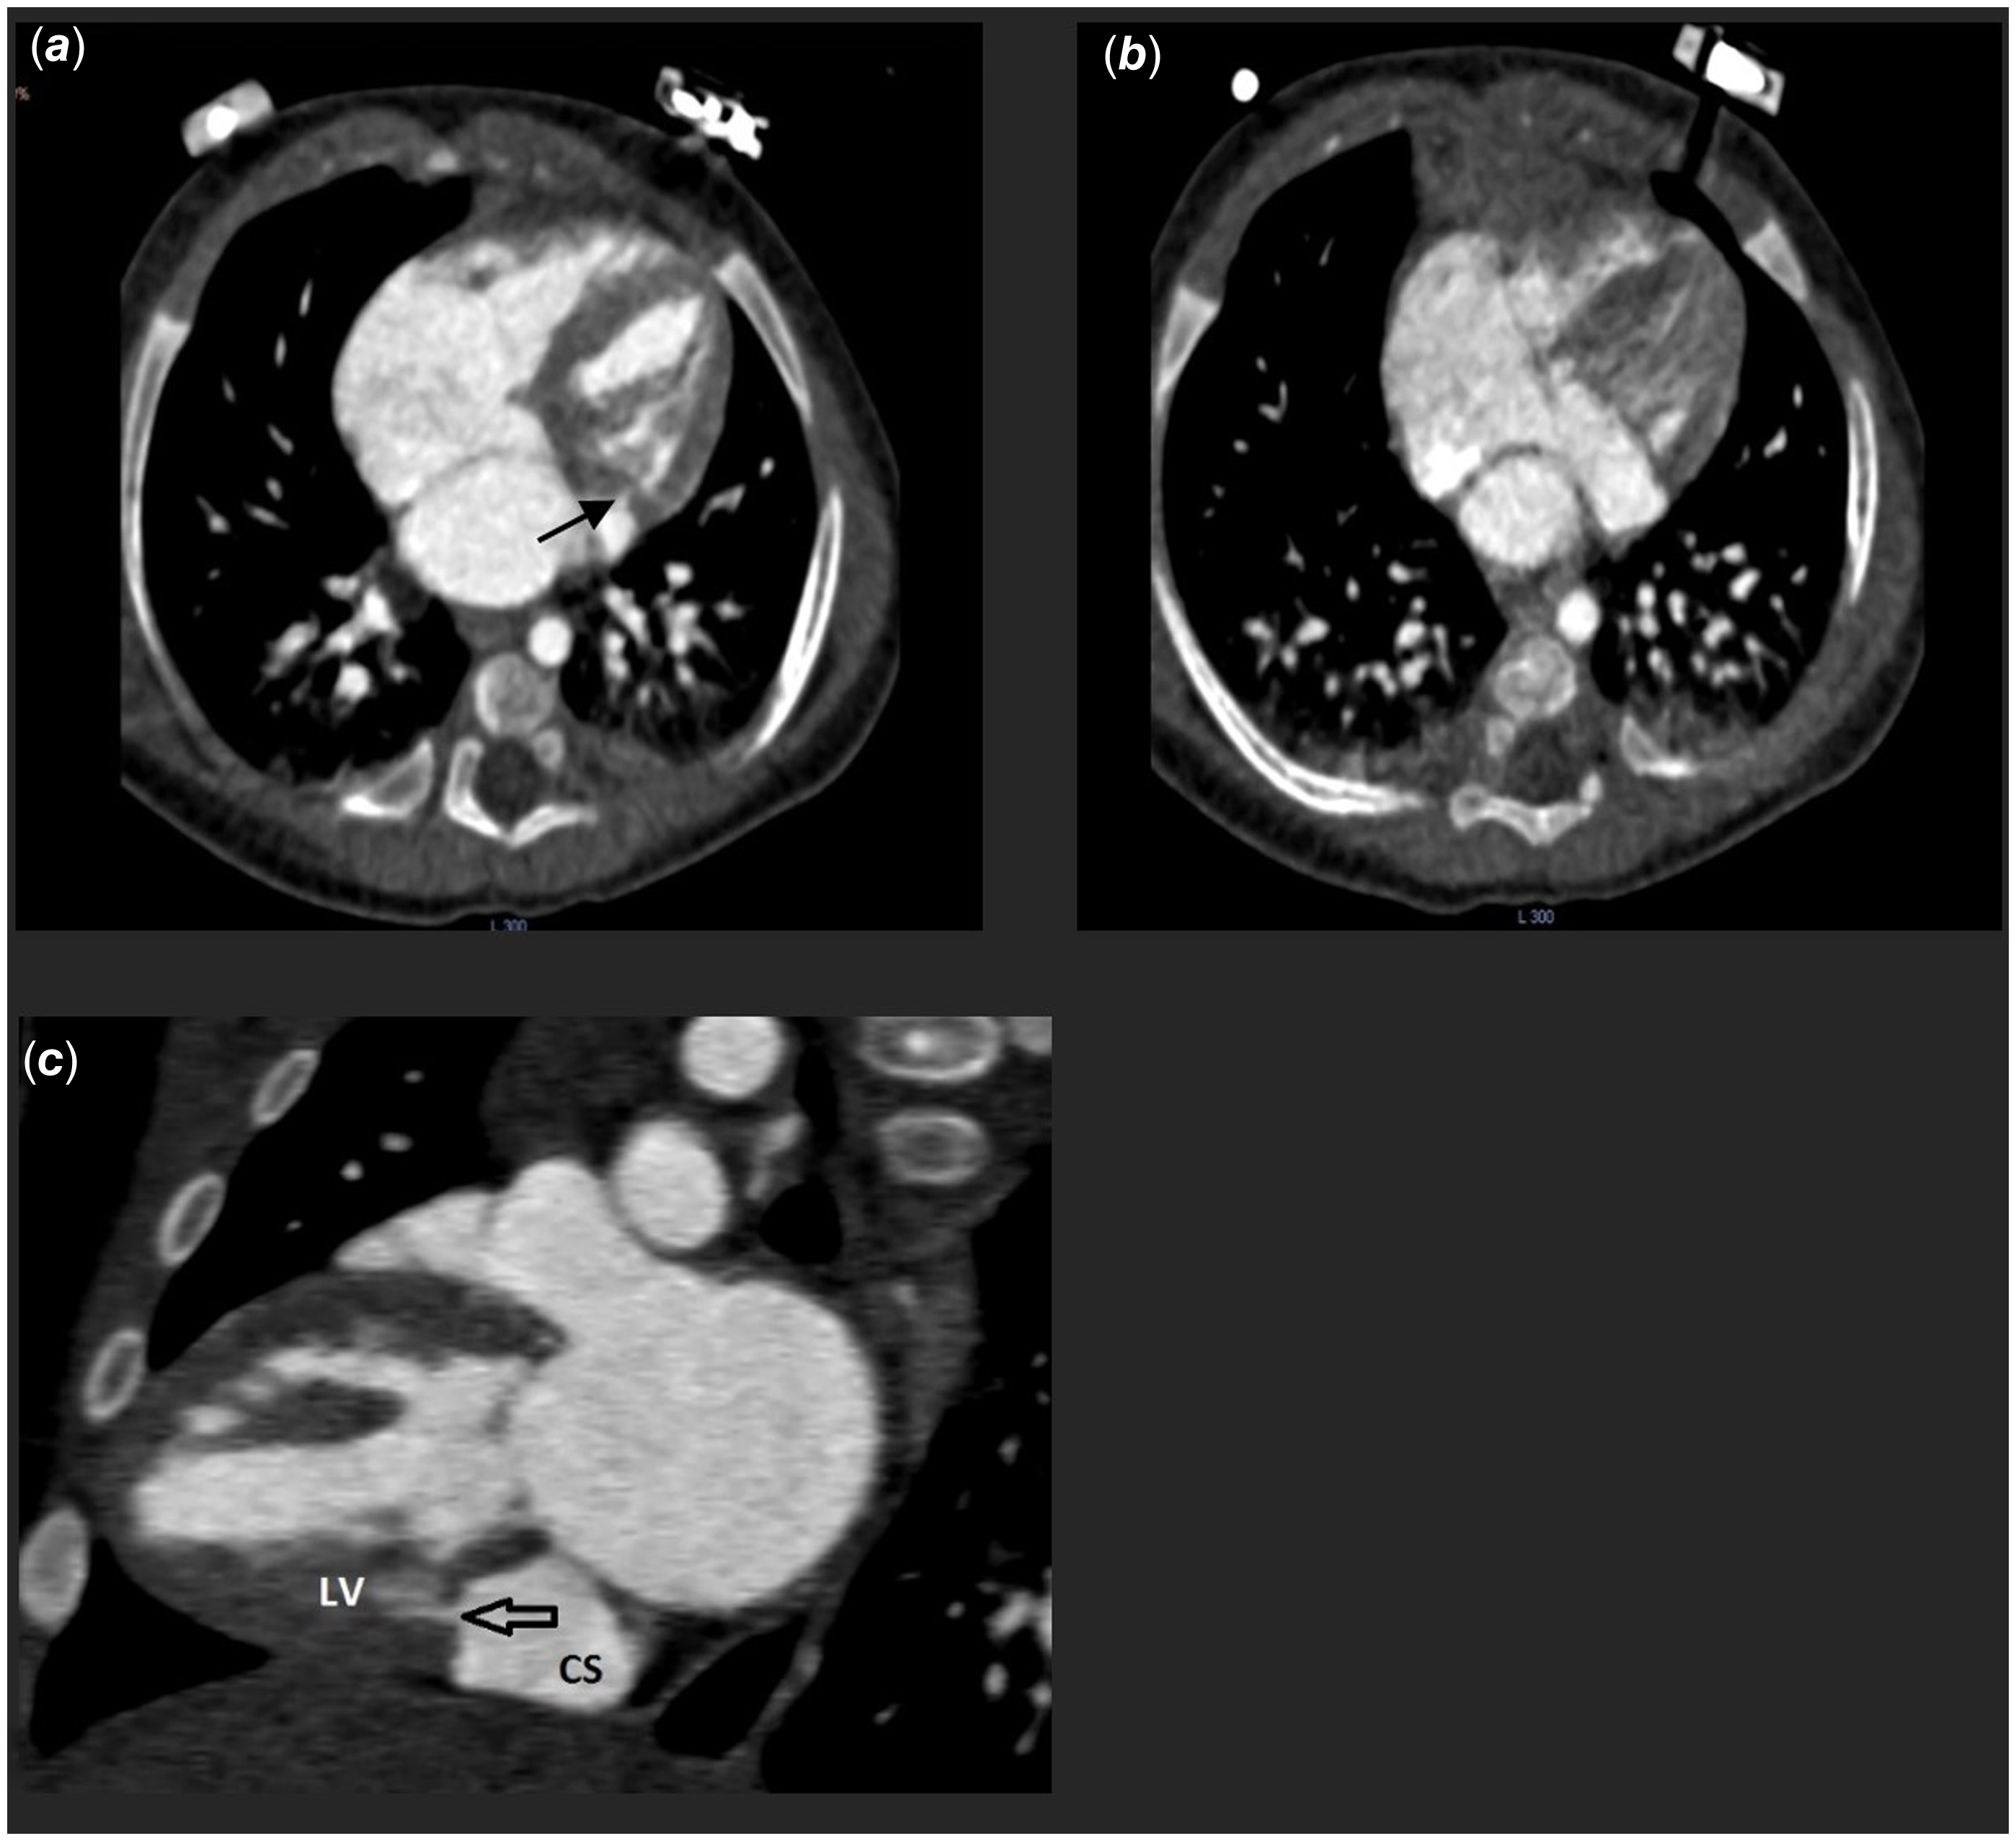

We report the case of an 18-month-old male, born full-term at 40 weeks without neonatal complications. At admission, his weight was 12 kg. The patient was acyanotic and asymptomatic. Cardiac examination revealed a prominent 3/6 systolic ejection murmur; however, there were no signs of heart failure or organomegaly, and weight gain was normal. Chest radiography indicated slight cardiomegaly, while the electrocardiogram showed sinus rhythm with a normal axis and no ST or T wave changes. A 2D and Doppler echocardiogram identified a dilated coronary sinus due to a left ventricular to coronary sinus fistula, with a jet waist measuring 3 mm and velocity around 4 m/sec. The pressure gradient across the fistula was noted at 60 mm Hg (Figure 1). Additionally, moderate right atrial enlargement and right ventricular enlargement were observed, with an Left Ventricular Ejection Fraction of 60%. Pre-procedural CT angiography provided a detailed anatomical evaluation, showing a width of 3 mm and a length of 4 mm (Figure 2). Catheterization revealed normal right atrial pressure and pulmonary artery pressures of 30/15 mmHg (mean 22 mmHg). Oxygen saturation levels indicated a significant left-to-right shunt with Qp/Qs of 1:1.5. Two catheterisation strategies, antegrade and retrograde, were evaluated for the occlusion procedure. Due to the intricate anatomical structure and the demanding wire-snaring location, the antegrade approach was favoured. This strategy facilitated traversal through the defect from the left ventricle to the coronary sinus, with successful snaring executed in the right atrium. In contrast, utilizing the retrograde approach would have necessitated wire snaring within the left ventricle, which was anticipated to be more challenging than the antegrade method. To close this fistula, a 4 French pig-tail catheter, which had been appropriately sized by trimming its tip, was first inserted into the left ventricle via the femoral artery. Subsequently, a 0.018-inch guidewire was used to traverse the fistula, and the wire was snared in the right atrium. After successfully navigating the fistula pathway, it was occluded using a Piccolo device (5 mm × 4 mm). The selection of this device was due to its optimal flexibility and the ability to conform to the anatomical configuration of the lesion. To ensure precise placement and maximum stability, the first disc of the device was positioned in the left ventricle, the body of the device within the fistula, and the final disc in the coronary sinus. Given the enlarged and dilated nature of the coronary sinus, positioning the edge of the device at the base of the coronary sinus did not interfere with the sinus pathway (Figure 3). Serial echocardiographic follow-ups before discharge and at 1, 6, 12, 24, and 32 months post-procedure showed minimal residual shunt initially, which resolved completely in subsequent studies with no shunt present at the fistula site (Figure 4). A 24-hour Holter monitor post-discharge confirmed normal sinus rhythm without ectopic beats or arrhythmias.

Figure 1. (a) The four-chamber view on the 2D echocardiogram reveals a dilated coronary sinus. (b,c) apical four-chamber view with colour Doppler showing the turbulent flow from the left ventricular (LV) to coronary sinus (CS). (d) A parasternal long-axis view with colour Doppler showing the fistula flow from the posterior-inferior aspect of the LV free wall to the CS. 2D, two-dimensional; CF, colour flow Doppler.